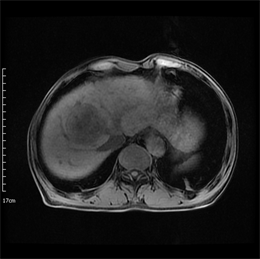

Figure 2. Axial MRI images of the same patient as in Figure 1 after TACE treatment. (a) T1-weighted unenhanced image shows a hypointensive lesion in right lobe of liver. (b) Arterial phase contrast-enhanced image shows the central necrotic area and peripheral enhanced area in the lesion. (c) ADC map. (d) Dslow map. (e) Dfast map. (f) f map.